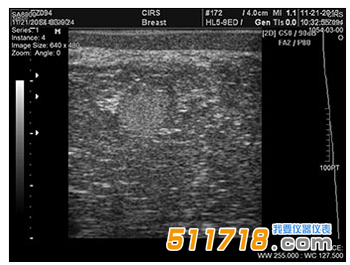

CIRS 073多模式乳房活檢和超聲波訓練模體 超聲波